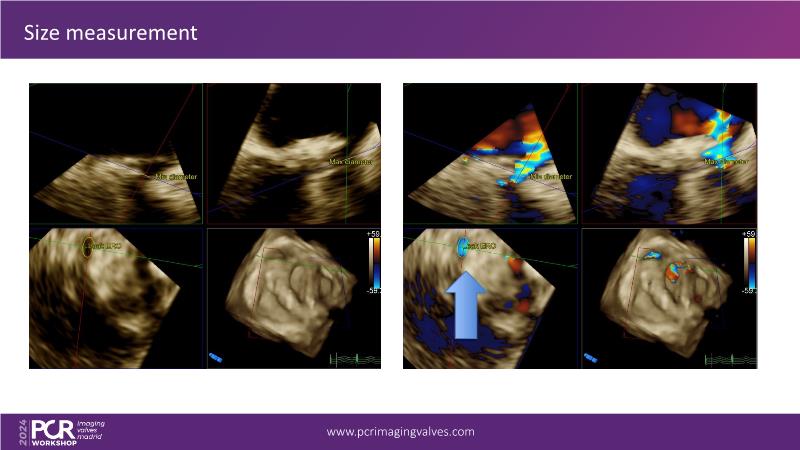

Explore cutting-edge transcatheter valve interventions for mitral and aortic valve disorders, including valve-in-valve procedures and management strategies for paravalvular leakages, and learn about diagnosing and treating mitral annular calcification and transcatheter options in infective endocarditis.

- To get tips and tricks for guidance of transcatheter intervention